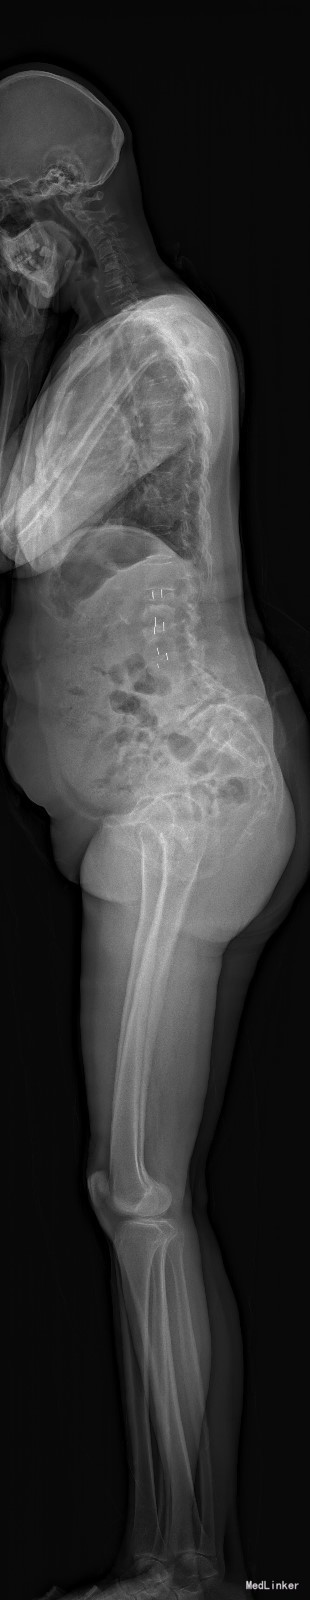

主诉:右下肢麻木11年,腰部酸痛无力 现病史:女性患者,65岁,患者于11年前无明显诱因下出现右下肢麻木,自大腿至右踝部,站立位加重。未予重视,后期出现腰臀部僵硬,弓背僵硬无力,自主行走距离不足200米,曾于06年经X线平片及MRI检查:腰椎椎管狭窄伴有腰椎滑脱,椎间盘突出等。

查体:侧弯畸形,右臀部及右下肢麻木疼痛,腰部活动受限,难以站立。右侧支腿抬高试验60°。双下肢肌力肌张力可。 辅助检查:平片:腰椎侧弯,椎体滑脱,曲度后凸 磁共振:L2-3,L4-5,L5-S1腰椎椎管狭窄,l2-3L3-4L4-5L5-S1腰椎间盘突出,腰椎退变

诊断: 腰椎侧弯,腰椎间盘突出 治疗:1期微创侧路椎体融合术+2期 微创后路经皮内固定术